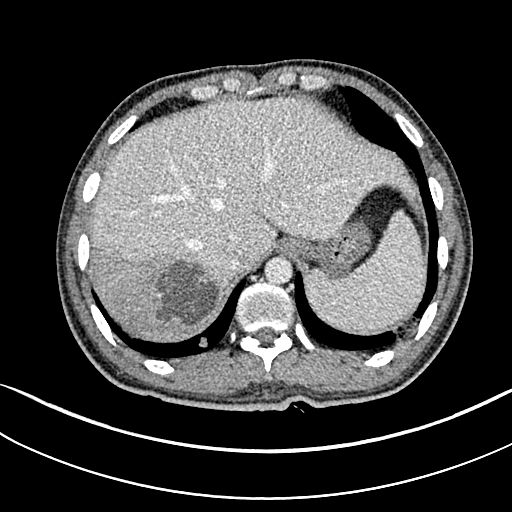

CT:双肺多发空洞、气囊、结节,病灶以胸膜下为主,见实变,胸腔积液。肝脓肿。

CT也提示脓毒肺栓塞!

这个患者的特点是肺空洞,肝脓肿!肝脓肿的存在,大大缩小了诊断范围,缩小了细菌范围!肺CT提示脓毒肺栓塞,并且同时存在肝脓肿,绝大多数都是肺炎克雷伯杆菌,不是金葡菌,真菌更是少见!